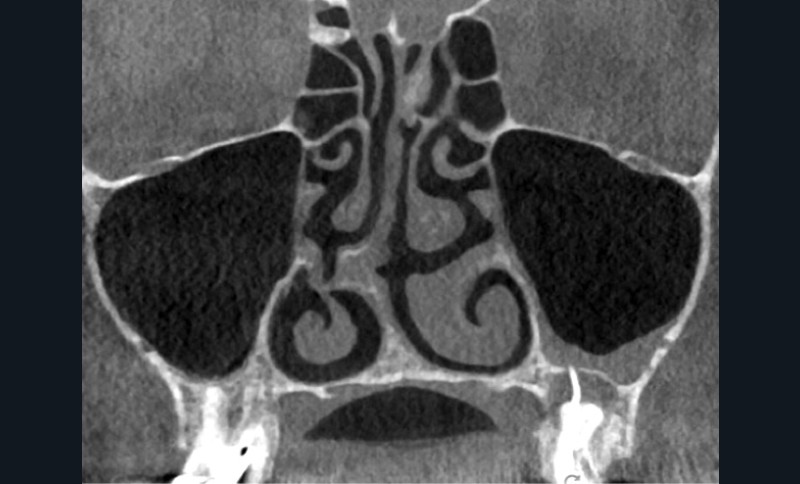

Si les isthmes sont particulièrement mis en évidence au niveau des molaires mandibulaires, cela devient médicalement important au niveau des molaires maxillaires.

La diffusion bactérienne et de leurs toxines, au niveau des molaires maxillaires est à l’origine d’un grand nombre de sinusites maxillaires chroniques, d’origine dentaire. Celles-ci sont principalement causées par l’absence de traitement du deuxième canal MV, qui existe dans 90 % des cas, et il est à noter que ces deux canaux – MV1 et MV2 – sont également reliés par un isthme.

Le nettoyage des isthmes intercanalaires reste un réel problème, et semble responsable de nombreux échecs [43]. Par ailleurs, il est nécessaire d’utiliser des instruments qui évitent de propulser les débris, tant apicalement que latéralement, en obturant les entrées isthmiques avec des débris compactés.